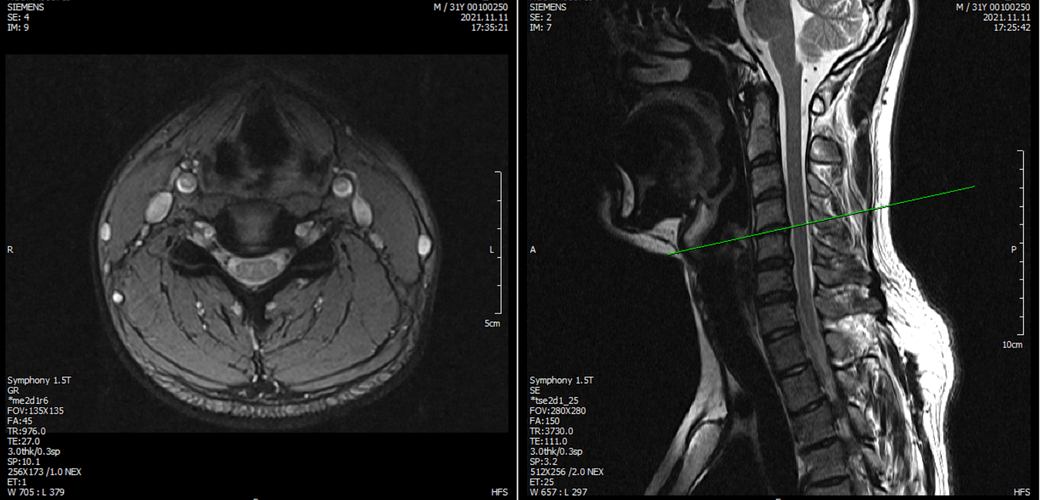

아래는 저의 경추과 요추 MRI 사진 첨부합니다.

• 1번 째 사진

• 2번 째 사진

• 3번 째 사진

• 4번 째 사진